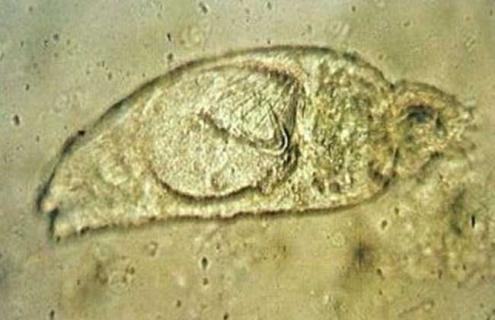

三代虫身体扁平纵长,前端有两个突起的头器,能够主动伸缩,又有单细胞腺的头腺一对,开口于头器的前端,此虫没有眼点,口位于头器下方中央,下通咽、食道和两条盲管状的肠在体2两侧。体后端的固着器为一大形的固着盘。盘中央有2个大锚,大锚之间由2条横捧相连,盘的边缘有16个小钩,有秩序地排列着。

三代虫是雌雄同体,为扁形动物门吸虫纲微生物,有卵巢2个及精巢一个,位于身体后部,为卵胎生,在卵巢的前方有未分裂的受精卵及发育的胚胎,在大胚胎内又有小胚胎,因此称为三代虫。